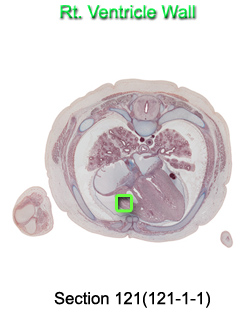

Tissue

–

Rt. Ventricle Wall

Carnegie Embryo #9226

Location:

121-01-01

Back to Section 121